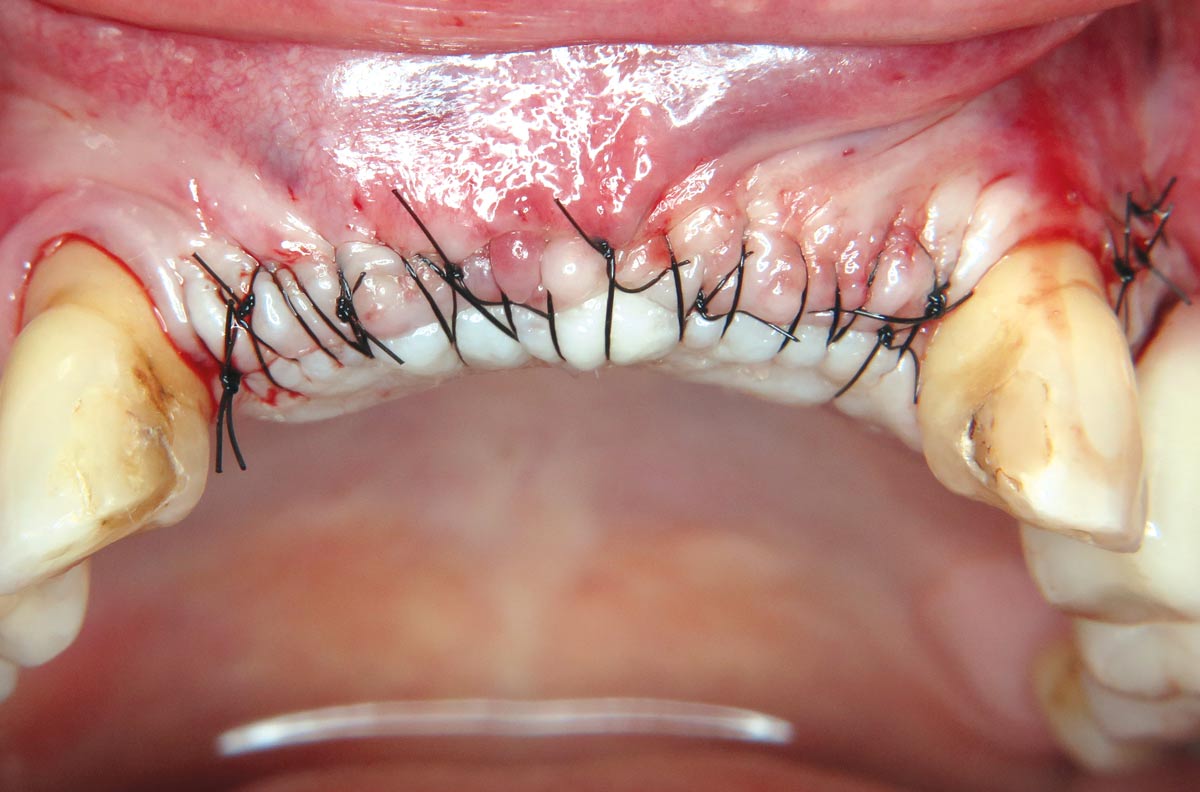

08 / 22 - Tension-free wound closure

Three-dimensional augmentation with maxgraft® cortico - M.Sc. E. Kapogianni